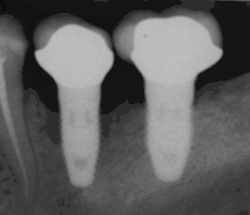

Primary implant stability

Primary implant stability refers to the stability of a dental implant immediately after implantation. The stability of the titanium screw implant in the patient's bone tissue post surgery may be non-invasively assessed using resonance frequency analysis. Sufficient initial stability may allow immediate loading with prosthetic reconstruction, though early loading poses a higher risk of implant failure than conventional loading.[90]

The relevance of primary implant stability decreases gradually with regrowth of bone tissue around the implant in the first weeks after surgery, leading to secondary stability. Secondary stability is different from the initial stabilization, because it results from the ongoing process of bone regrowth into the implant (osseointegration). When this healing process is complete, the initial mechanical stability becomes biological stability. Primary stability is critical to implantation success until bone regrowth maximizes mechanical and biological support of the implant. Regrowth usually occurs during the 3–4 weeks after implantation. Insufficient primary stability, or high initial implant mobility, can lead to failure.

An implant is tested between 8 and 24 weeks to determine if it is integrated. There is significant variation in the criteria used to determine implant success, the most commonly cited criteria at the implant level are the absence of pain, mobility, infection, gingival bleeding, radiographic lucency or peri-implant bone loss greater than 1.5 mm.[92]